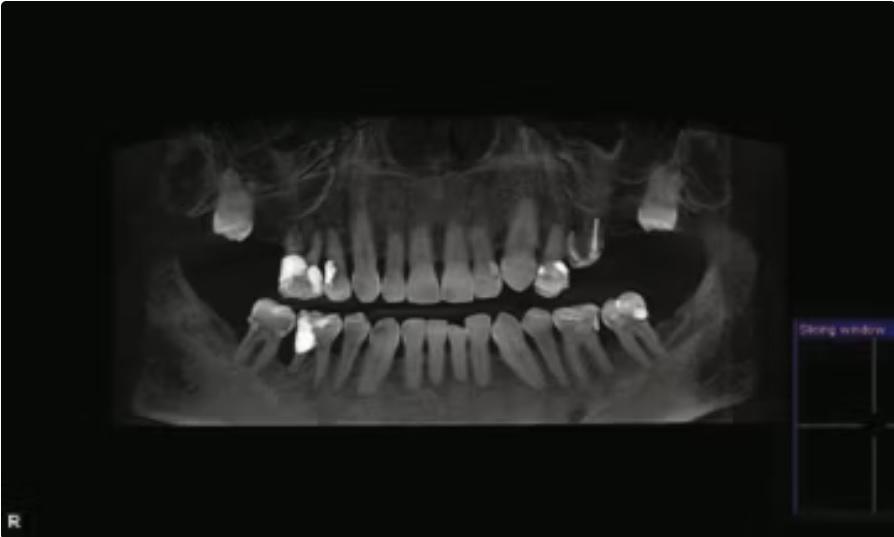

Панорамная рентгенограмма после удаления всех жевательных зубов, за исключением первых нижних премоляров. Пораженные третьи моляры не были удалены из-за явного риска анкилоза и потенциального повреждения задней стенки и дна верхнечелюстной пазухи.